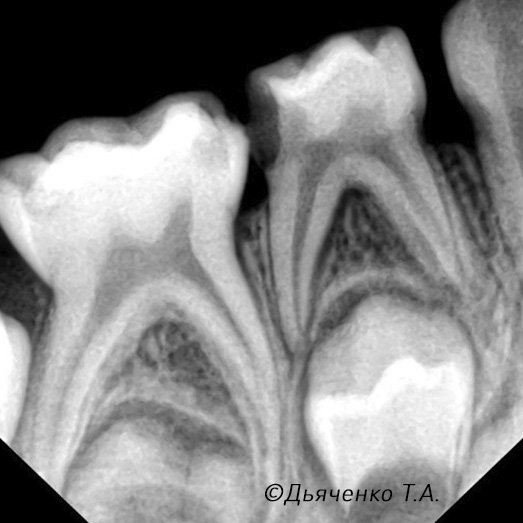

Особенность строения молочных зубов в том, что у них большая пульповая камера (полость зуба), стенки тонкие (эмаль и дентин). Именно поэтому кариозный процесс довольно быстро распространяется на сосудисто-нервный пучок и возникает пульпит.

Лечение пульпита у детей

Перед началом лечения стоматолог проводит сбор анамнеза — выясняет, на что жалуется ребёнок, как давно появилась боль, усиливается ли она ночью или при контакте с холодным и горячим. Затем выполняется осмотр полости рта и делается рентгеновский снимок — прицельный или ортопантомограмма, чтобы оценить степень поражения зуба, состояние корней и окружающих тканей.